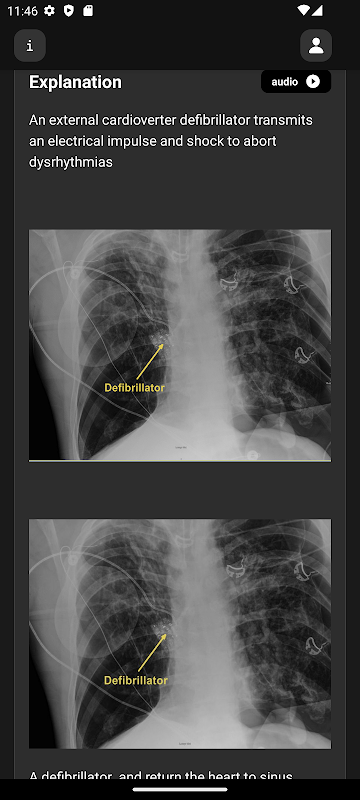

Radiologische afbeeldingen, video's en animaties van hoge kwaliteit